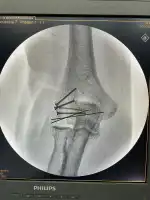

Galería de Praxis Moritz Sporleder